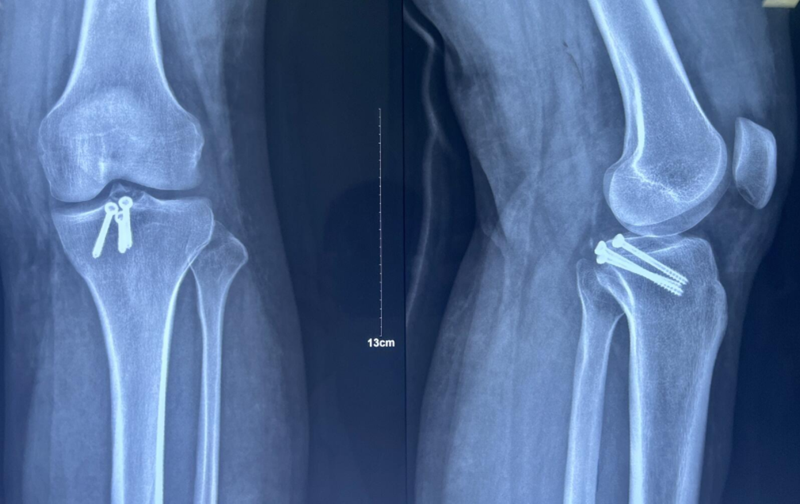

x男,30岁,体重100kg,在五楼擦玻璃时坠落到四楼致伤2天。

诊断:左胫骨平台后柱骨折,后交叉韧带撕脱骨折,左踝关节pilon骨折3型。

术前影像学资料:

图7 前交叉韧带撕脱骨折与平台后柱骨折

图8 Pilon骨折3型

术后影像学资料: